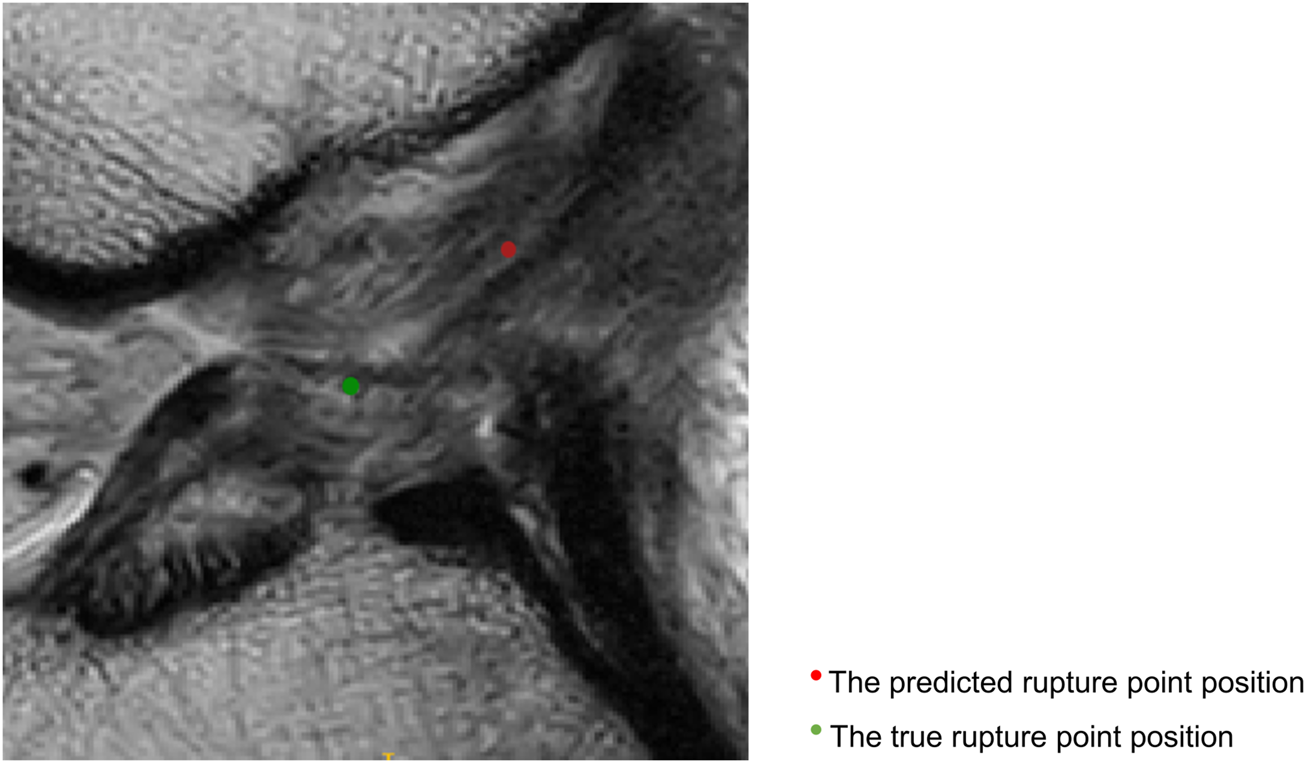

Figure 5 shows that the predicted rupture point location is very close to the true rupture point location and the Euclidean distance between them is within the set error range. The deep learning model is able to correctly locate the ACL rupture point and therefore outputs the correct classification.

FIGURE 5. Sagittal views of the cropped MR image, correct localization and classification. The predicted rupture point is marked by red circle, while the true rupture point is green. The model predicted a correct localization, and the system shows a correct classification (the middle side).